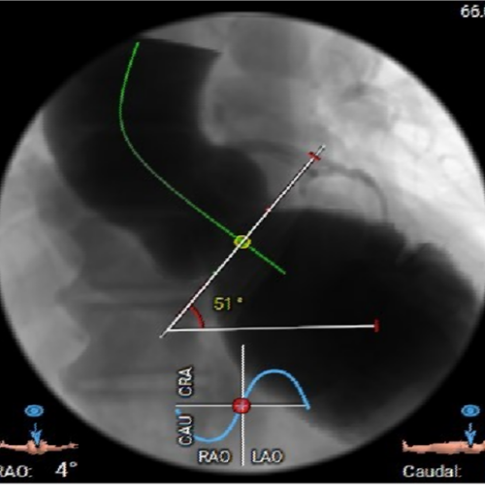

· 主动脉瓣环水平夹角51度,非横位心,主动脉弓宽度、角度尚可,弓部存在散在钙化;

虚拟瓣环与水平夹角

· 水平夹角51度,非横位心,主动脉弓宽度、角度尚可,弓部存在散在钙化,预估输送器过弓顺利,跨瓣难度增高,必要时采用Snare辅助。